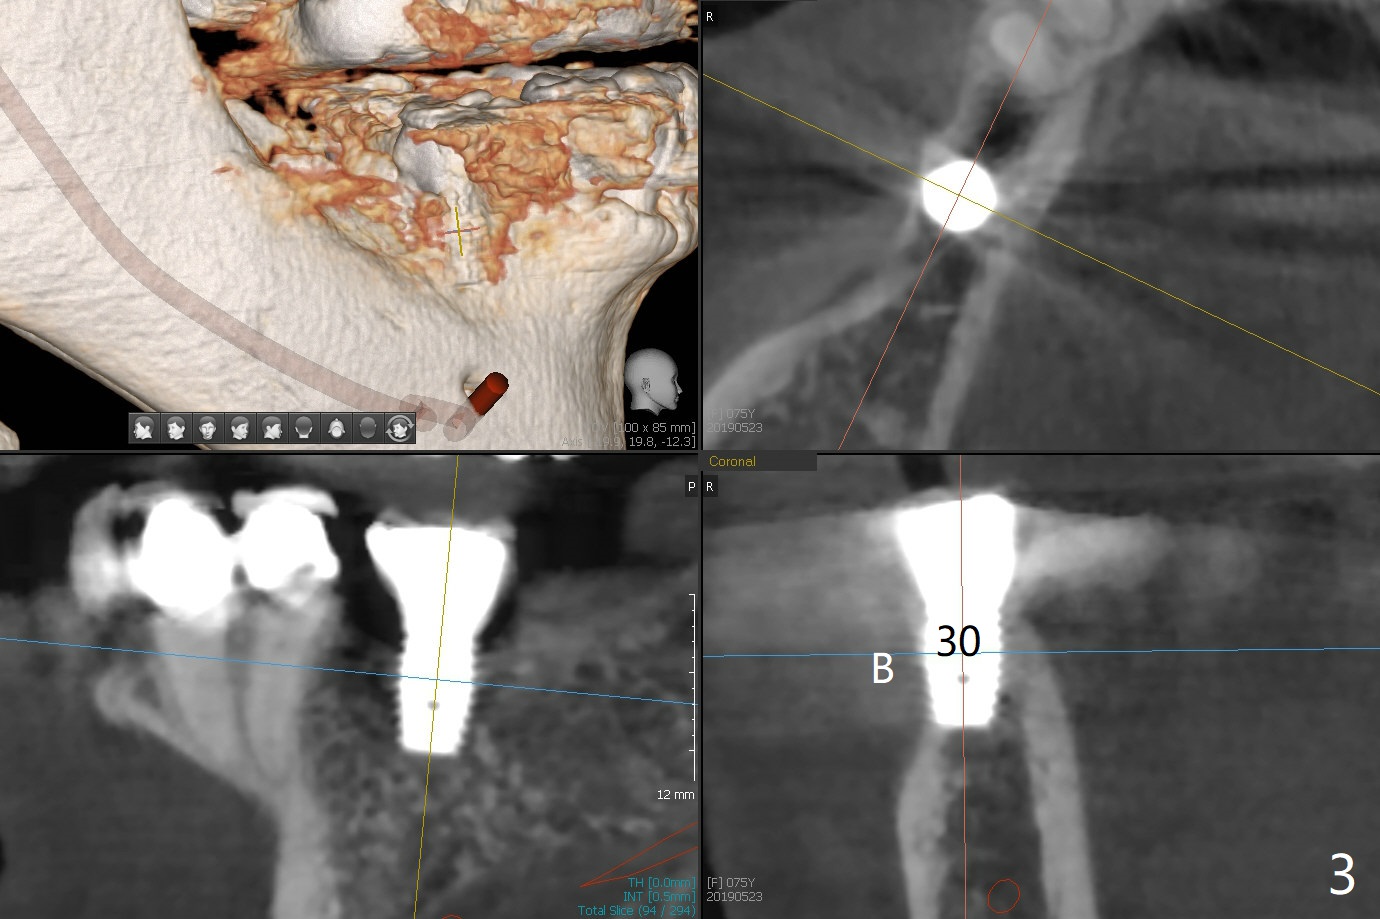

When the 75-year-old woman presents to clinic with #25 mobility, she is also concerned about gingival hemorrhage. It appears that the buccal plate is lost at #10 and 30 (Fig.2,3), as compared to #7, 19, 20 (Fig.1,4,5). Block graft may be required (Fig.6,7 for #10 for example). In fact there is tenderness buccal to the implant at #30. The patient has been using water pik and will carry it while traveling.